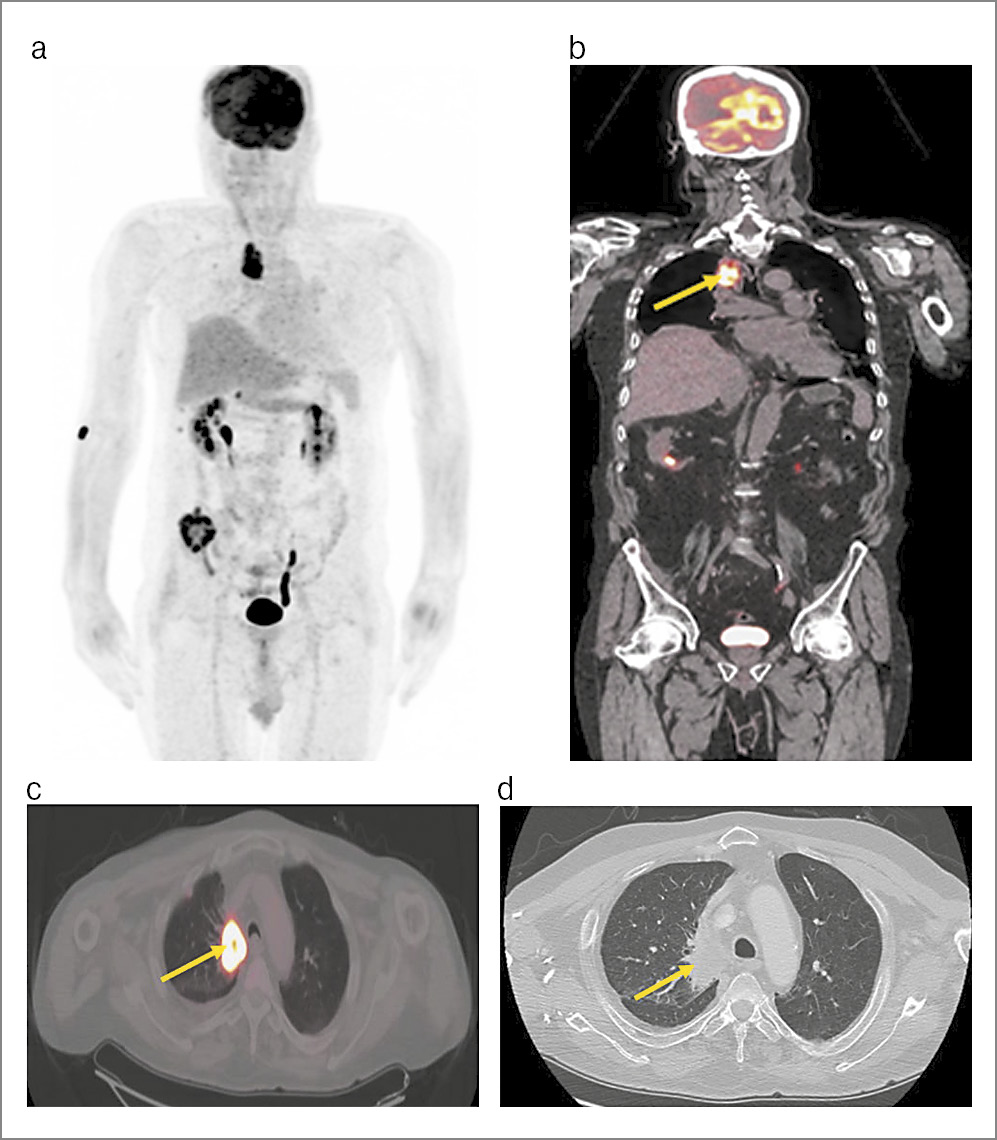

По данным ПЭТ/КТ в верхней доле правого легкого имеется объемное образование с лучистыми контурами, с наличием участков некроза в центральных отделах, размером 47×30 мм с гиперфиксацией РФП, а величина стандартизированного коэффициента максимального накопления составила 13,29. Опухоль распространяется в средостение с частичной обтурацией SI бронха. Определяются одиночные верхнемедиастинальные лимфоузлы справа с метаболической активностью SUVmax до 2,07. Диагностирована опухоль правого легкого неопластического характера с вовлечением в специфический процесс лимфоузлов средостения (рис. 3).

Рис. 3. Пациент Б., 56 лет: a – MIP-проекция ПЭТ; b – коронарная проекция ПЭТ-исследования; c – аксиальная проекция ПЭТ-исследования; d – аксиальная проекция КТ-исследования. В правом легком в верхней доле парамедиастинально определяется опухоль с лучистыми контурами, размером 47×30 мм, с повышенным метаболизмом 18F-ФДГ, SUVmax 13,29. Опухоль распространяется в средостение с неполной обтурацией SI бронха.